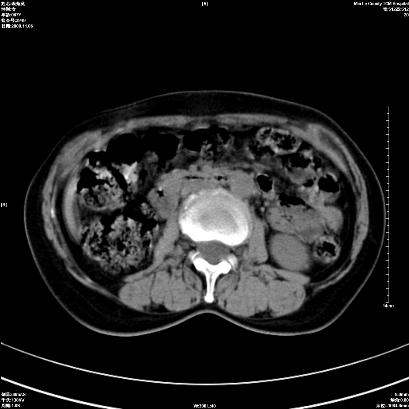

以下是引用卜一在2008-11-6 15:58:00的发言:[br]胰头略增大,胆总管扩张,末端渐行性狭窄。多考虑:胰头癌!建议增强!

以下是引用huangyinshan在2008-11-6 16:32:00的发言:[br]胰头略增大,胆总管扩张,末端渐行性狭窄。多考虑:胰头癌!建议增强!